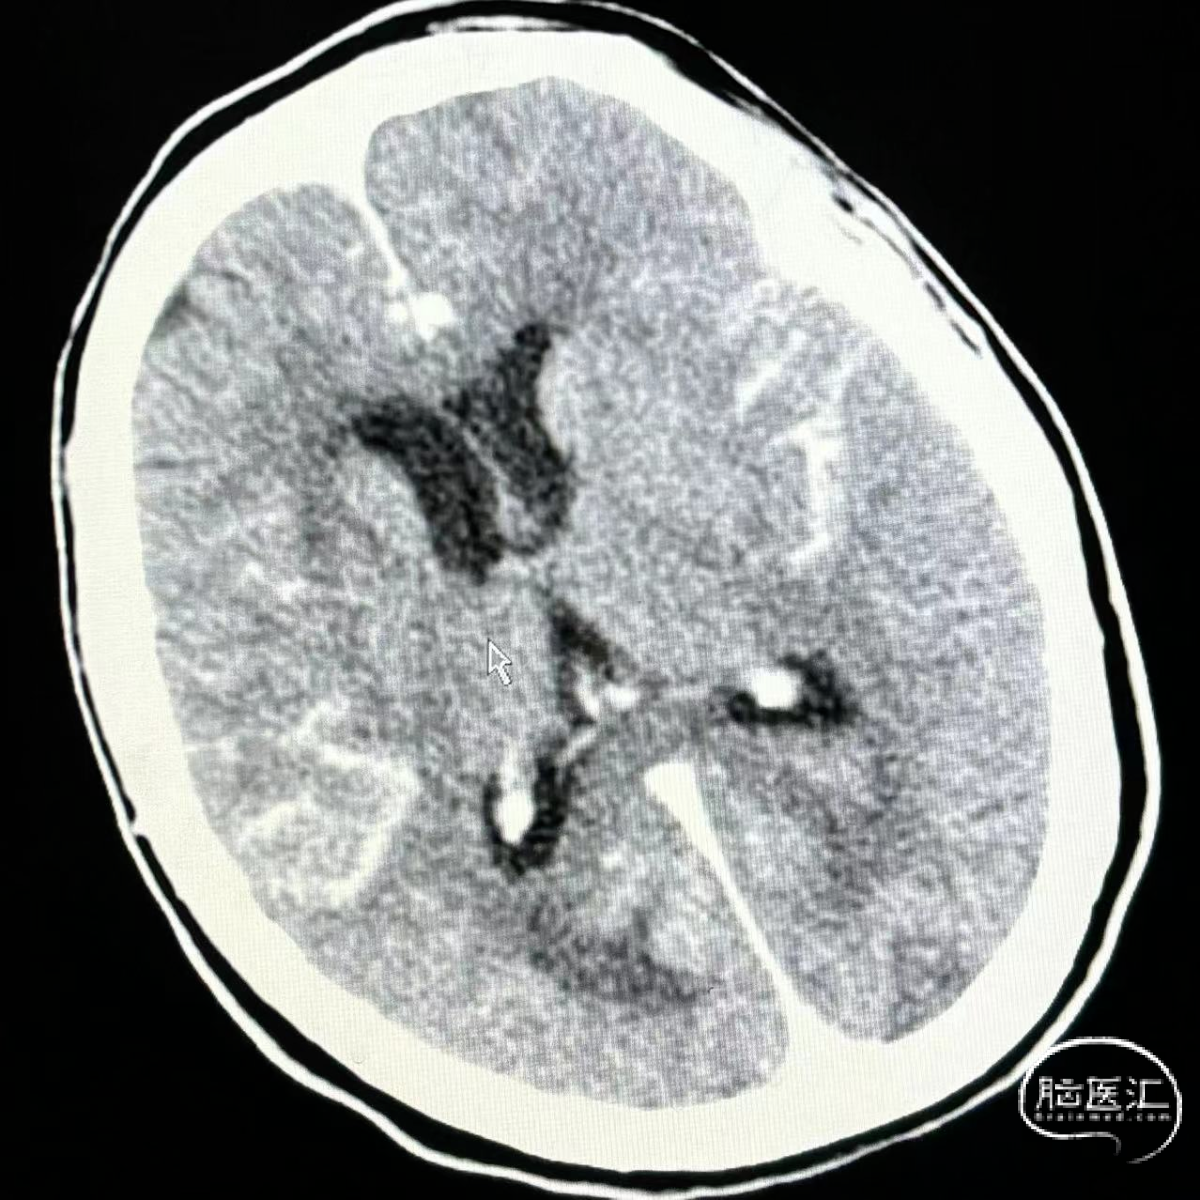

患者:女,78岁,SAH。

形态不规则,多发子瘤,WEB封闭近端瘤体,出院mRS 2分。